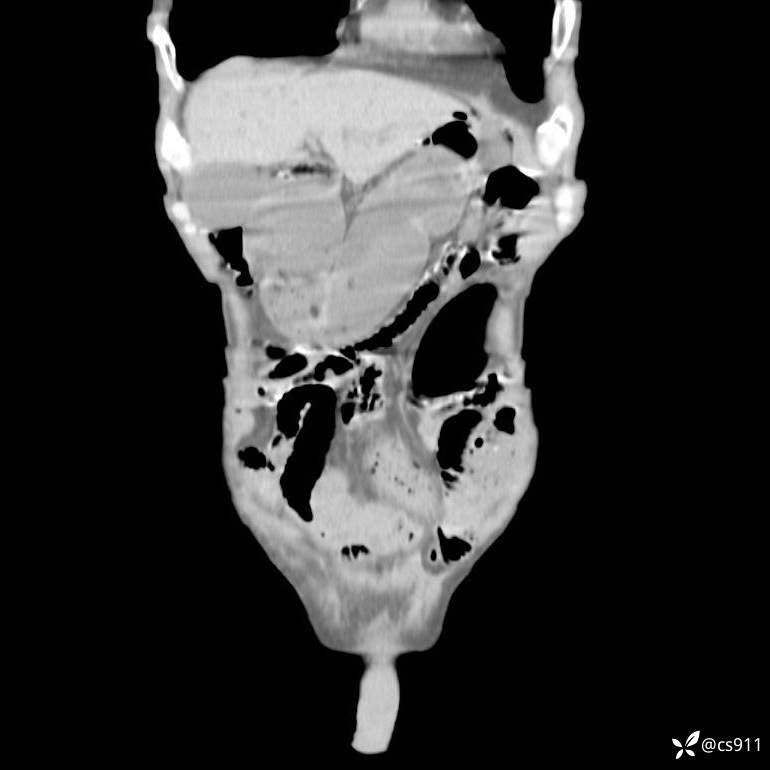

急腹症之急诊CT,原因?答案公布

男,77岁,腹痛、腹胀伴恶心呕吐1天。呕吐胃内容物,非喷射性呕吐,有咖啡色样胃内容物,诉有胃穿孔病史。查体:全腹平,下腹部压痛,全腹无反跳痛,叩诊呈浊音,移动性浊音阴性,肠鸣音减弱,1-2次/分。肛检:直肠未扪及明显肿物,可触及大量粪块。

T 36.6℃ P 80次/分 R 26次/分 BP 100/60mmHg

白细胞(WBC) H 14.55 10e9/L 4-10

中性粒细胞百分率(NEUT%) H 85.7 % 40-75

血淀粉酶(AMY) HH 1859 U/L 35-135

癌胚抗原(CEA) H 27.44 ng/ml 0-5

呕吐物 潜血试验 * 阳性 阴性

患者轮椅入室检查神志清楚, 能配合摆位和呼吸